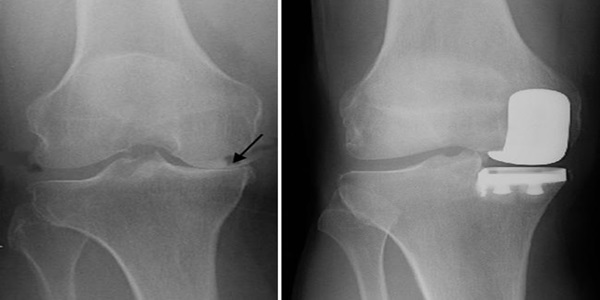

• X-ray used to determine the bone alignment and arthritis

The knee arthroscopy treatment in Gurgaon entails utilization of an arthroscope (small camera) into the knee joint by using keyhole incisions. This enables the surgeon to look into the knee and undertake some correctional actions by use of special tools. Determined as minimally invasive knee surgery in Gurgaon, unlike the rest of the open surgeries, does not result in as much tissue damage, pain, and recovery.

• The initial arthritis alterations